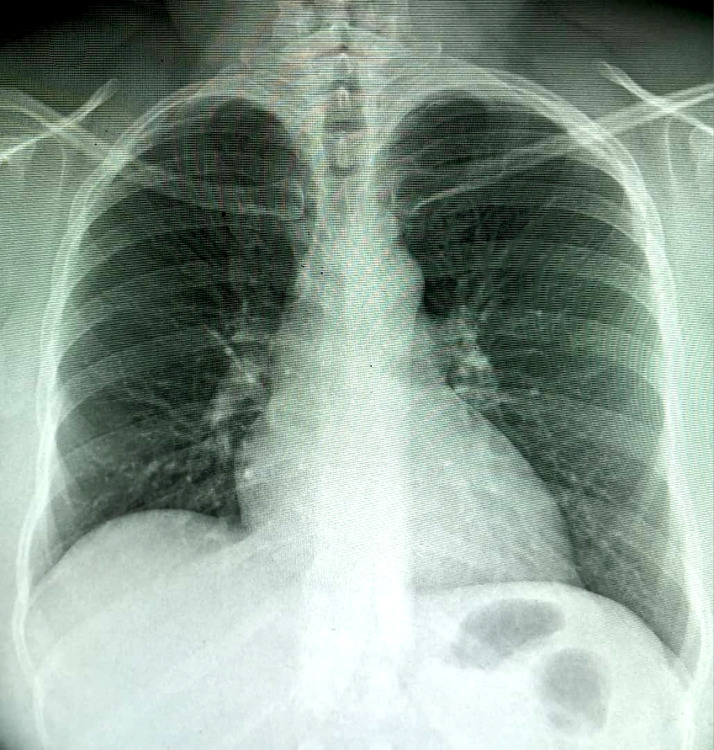

Introduction/rationale: Tuberculosis remains a major public health issue. It is an opportunistic pathology, very common in HIV-immunocompromised persons, classifying it at the WHO stage 4. Ear tuberculosis remains a rare and under-diagnosed clinical form. We report here a case of ear tuberculosis concomitant with pulmonary localization in an HIV-immunosuppressed person on triple antiretroviral therapy aged 32 years hospitalized in Bamako (Mali) to discuss the diagnostic and therapeutic difficulties posed by this rare localization.

Description of the case: The patient had a chronic productive cough, otalgia and right chronic purulent otorrhea. The search for acid-resistant bacilli was positive for direct examination in gastric casing fluid and swabbing of the ear pus, confirming the diagnosis of tuberculosis. Anti-tuberculosis treatment instituted for 6 months associated with adjuvants resulted in complete healing of the patient.